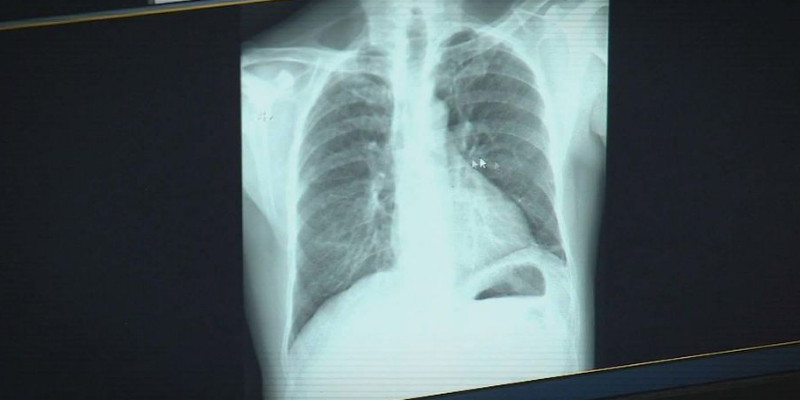

Ilustrasi/9News

rmol news logo Ratusan pekerja yang terlibat dalam proyek terowongan bawah tanah terbesar di Queensland diperkirakan akan menderita silikosis, yaitu penyakit paru-paru berbahaya dan bisa mematikan.

Silikosis adalah penyakit paru-paru yang tidak bisa disembuhkan, disebabkan oleh menghirup debu silika dalam jangka waktu lama. Penyakit ini sebelumnya sering dikaitkan dengan industri pemotongan batu buatan.